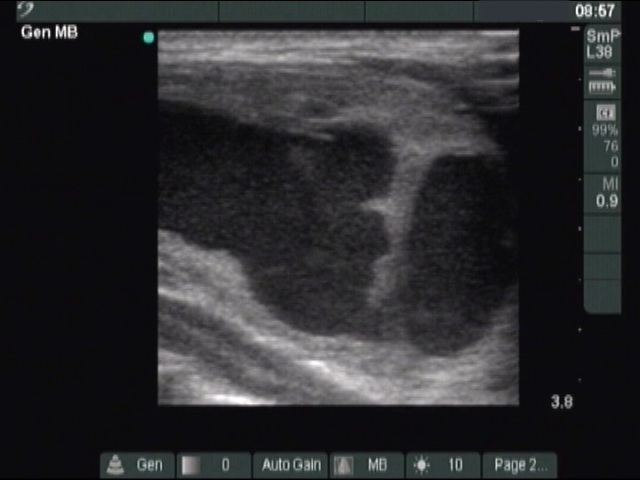

Ultrasonography: The thyroid was echonormal. A large cystic nodule composed of multiple chambers occupied almost the entire right lobe. Several fibrotic bundles dividing the chambers of the cyst were ruptured. The nodule presented halo sign and perinodular blood flow.